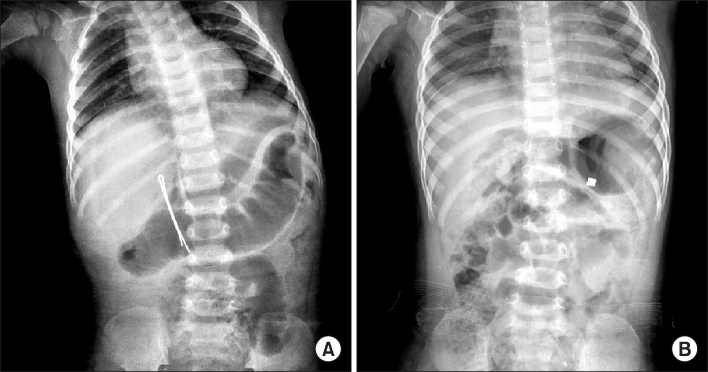

Fig. 2.

(A) Impaction of foreign body in appendix (gold accessory). (B) Impaction of foreign body in small intestine (hair pin).

Fig. 3.

(A) Perforation of duodenal second portion by hair pin. (B) Perforation of gastric greater curvature and jejunum by two magnets.

Fig. 2. (A) Impaction of foreign body in appendix (gold accessory). (B) Impaction of foreign body in small intestine (hair pin).

Fig. 3. (A) Perforation of duodenal second portion by hair pin. (B) Perforation of gastric greater curvature and jejunum by two magnets.